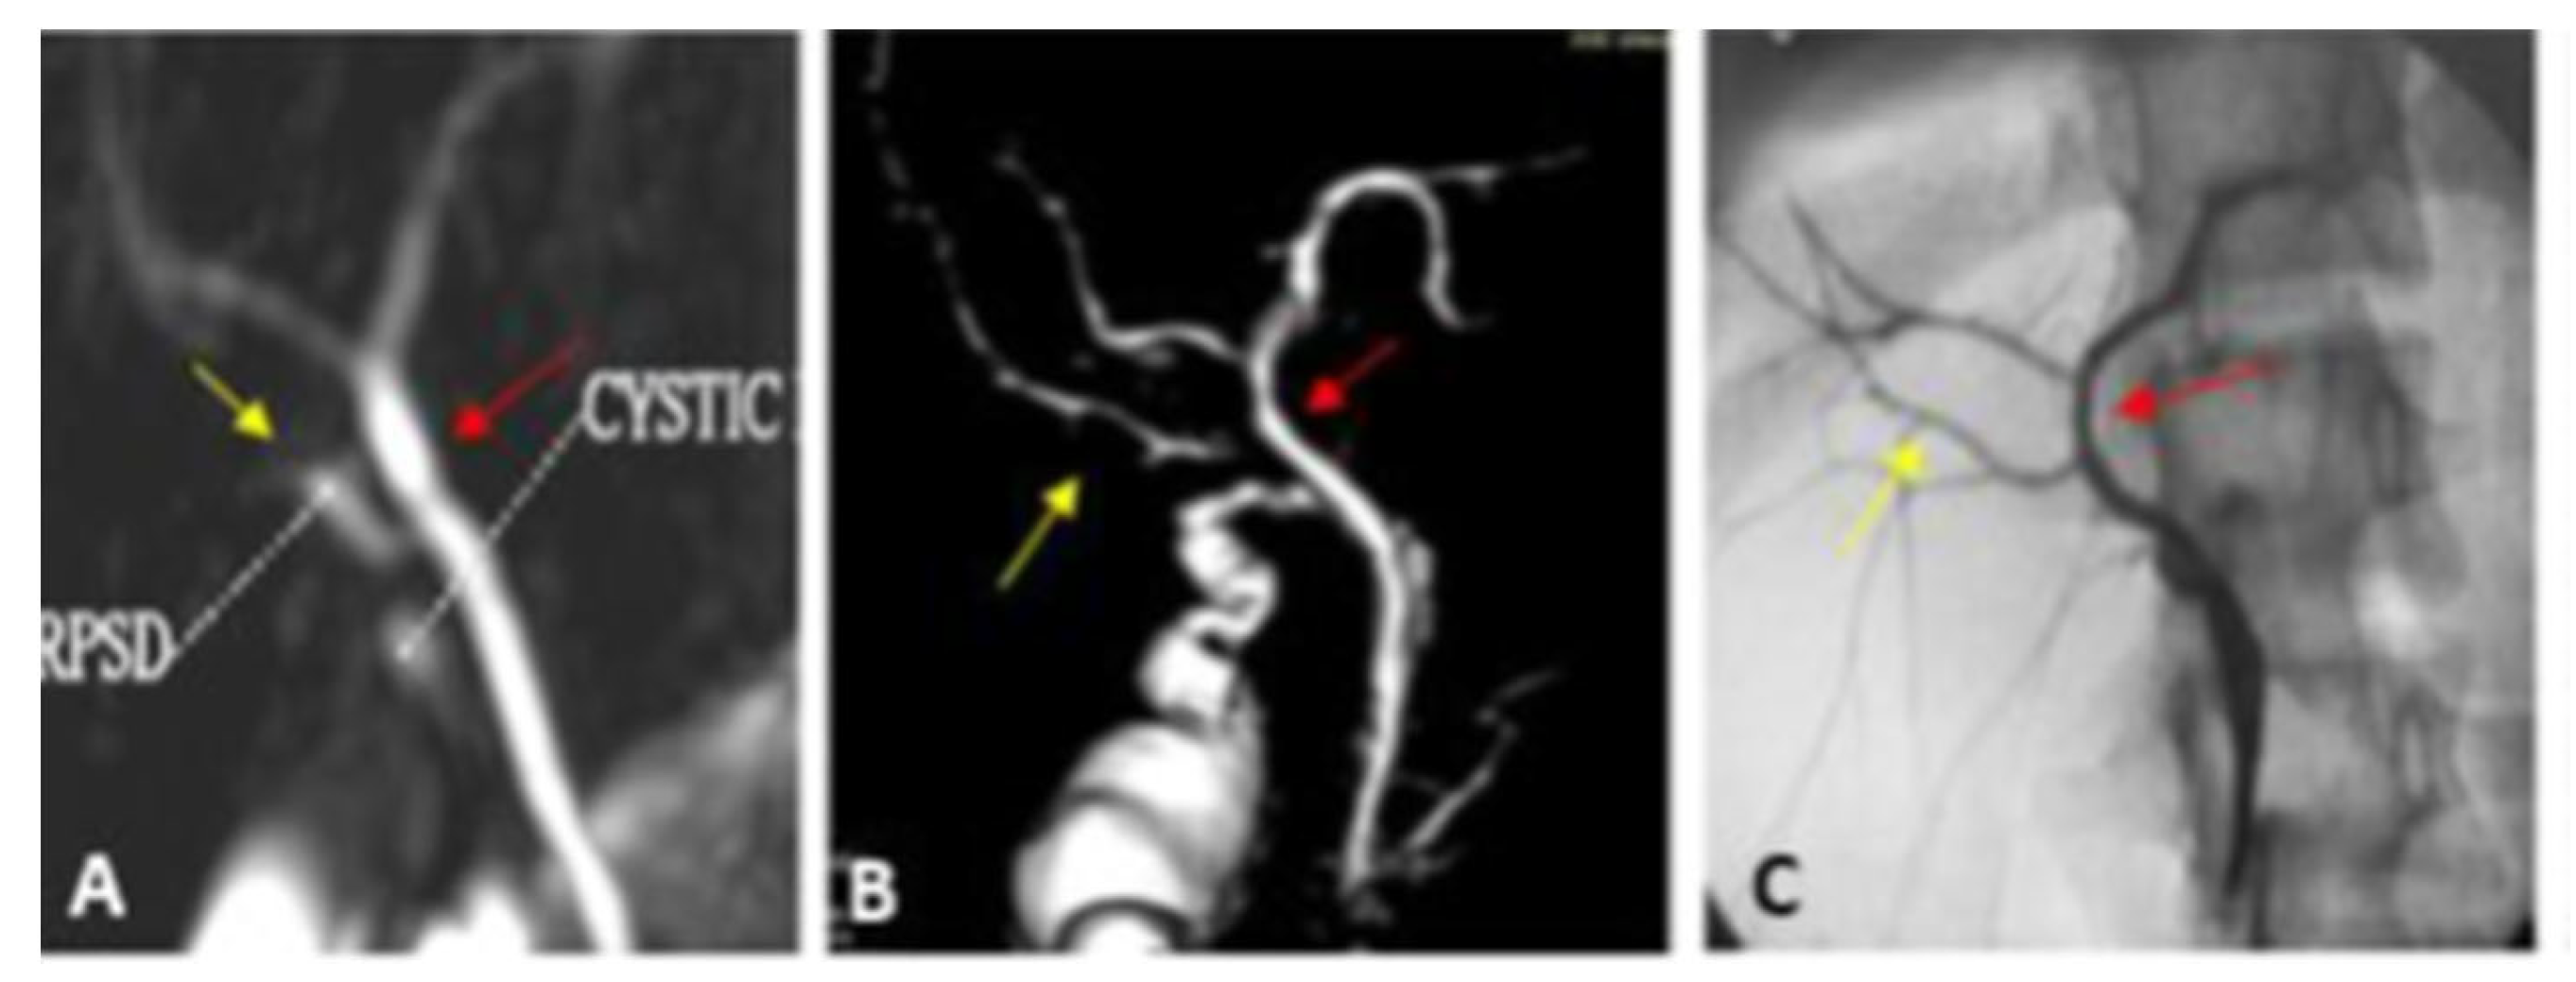

| Type I | The RPSD drains into the proximal part of the RHD (distance more than 1 cm from the hepatic confluence) | 23 (65.7) | 22 (62.9) | Very short RHD |

| Type II | Trifurcation | 4 (11.4) | 6 (17.1) | |

| Type III | Anomalous RPSD insertion | 4 (11.4) | 4 (11.4) | |

| A | Insertion of RP into the LT hepatic duct | 2 | 2 | |

| B | Insertion of RP into the CHD | 2 | 2 | |

| C | Insertion of RP into the cystic duct | - | - | |

| Type IV | Insertion of RHD in the cystic duct | 3 (8.6) | 3 (8.6) | |

| Type VII Unclassified | Trifurcation + accessory duct | 1 (2.9) | - | The acute angle between RPSD and RASD |